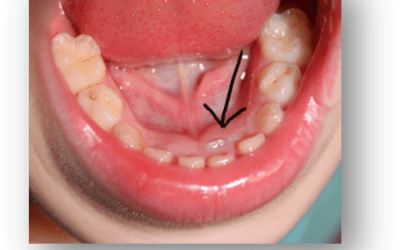

Lower Incisor Crowding

It can be exciting for children to start getting their first wriggly teeth. It will be the lower front teeth in the middle, usually between 5-6 years old. But to the concern of many parents, they have a look only to see the adult incisors coming up on the inside of...